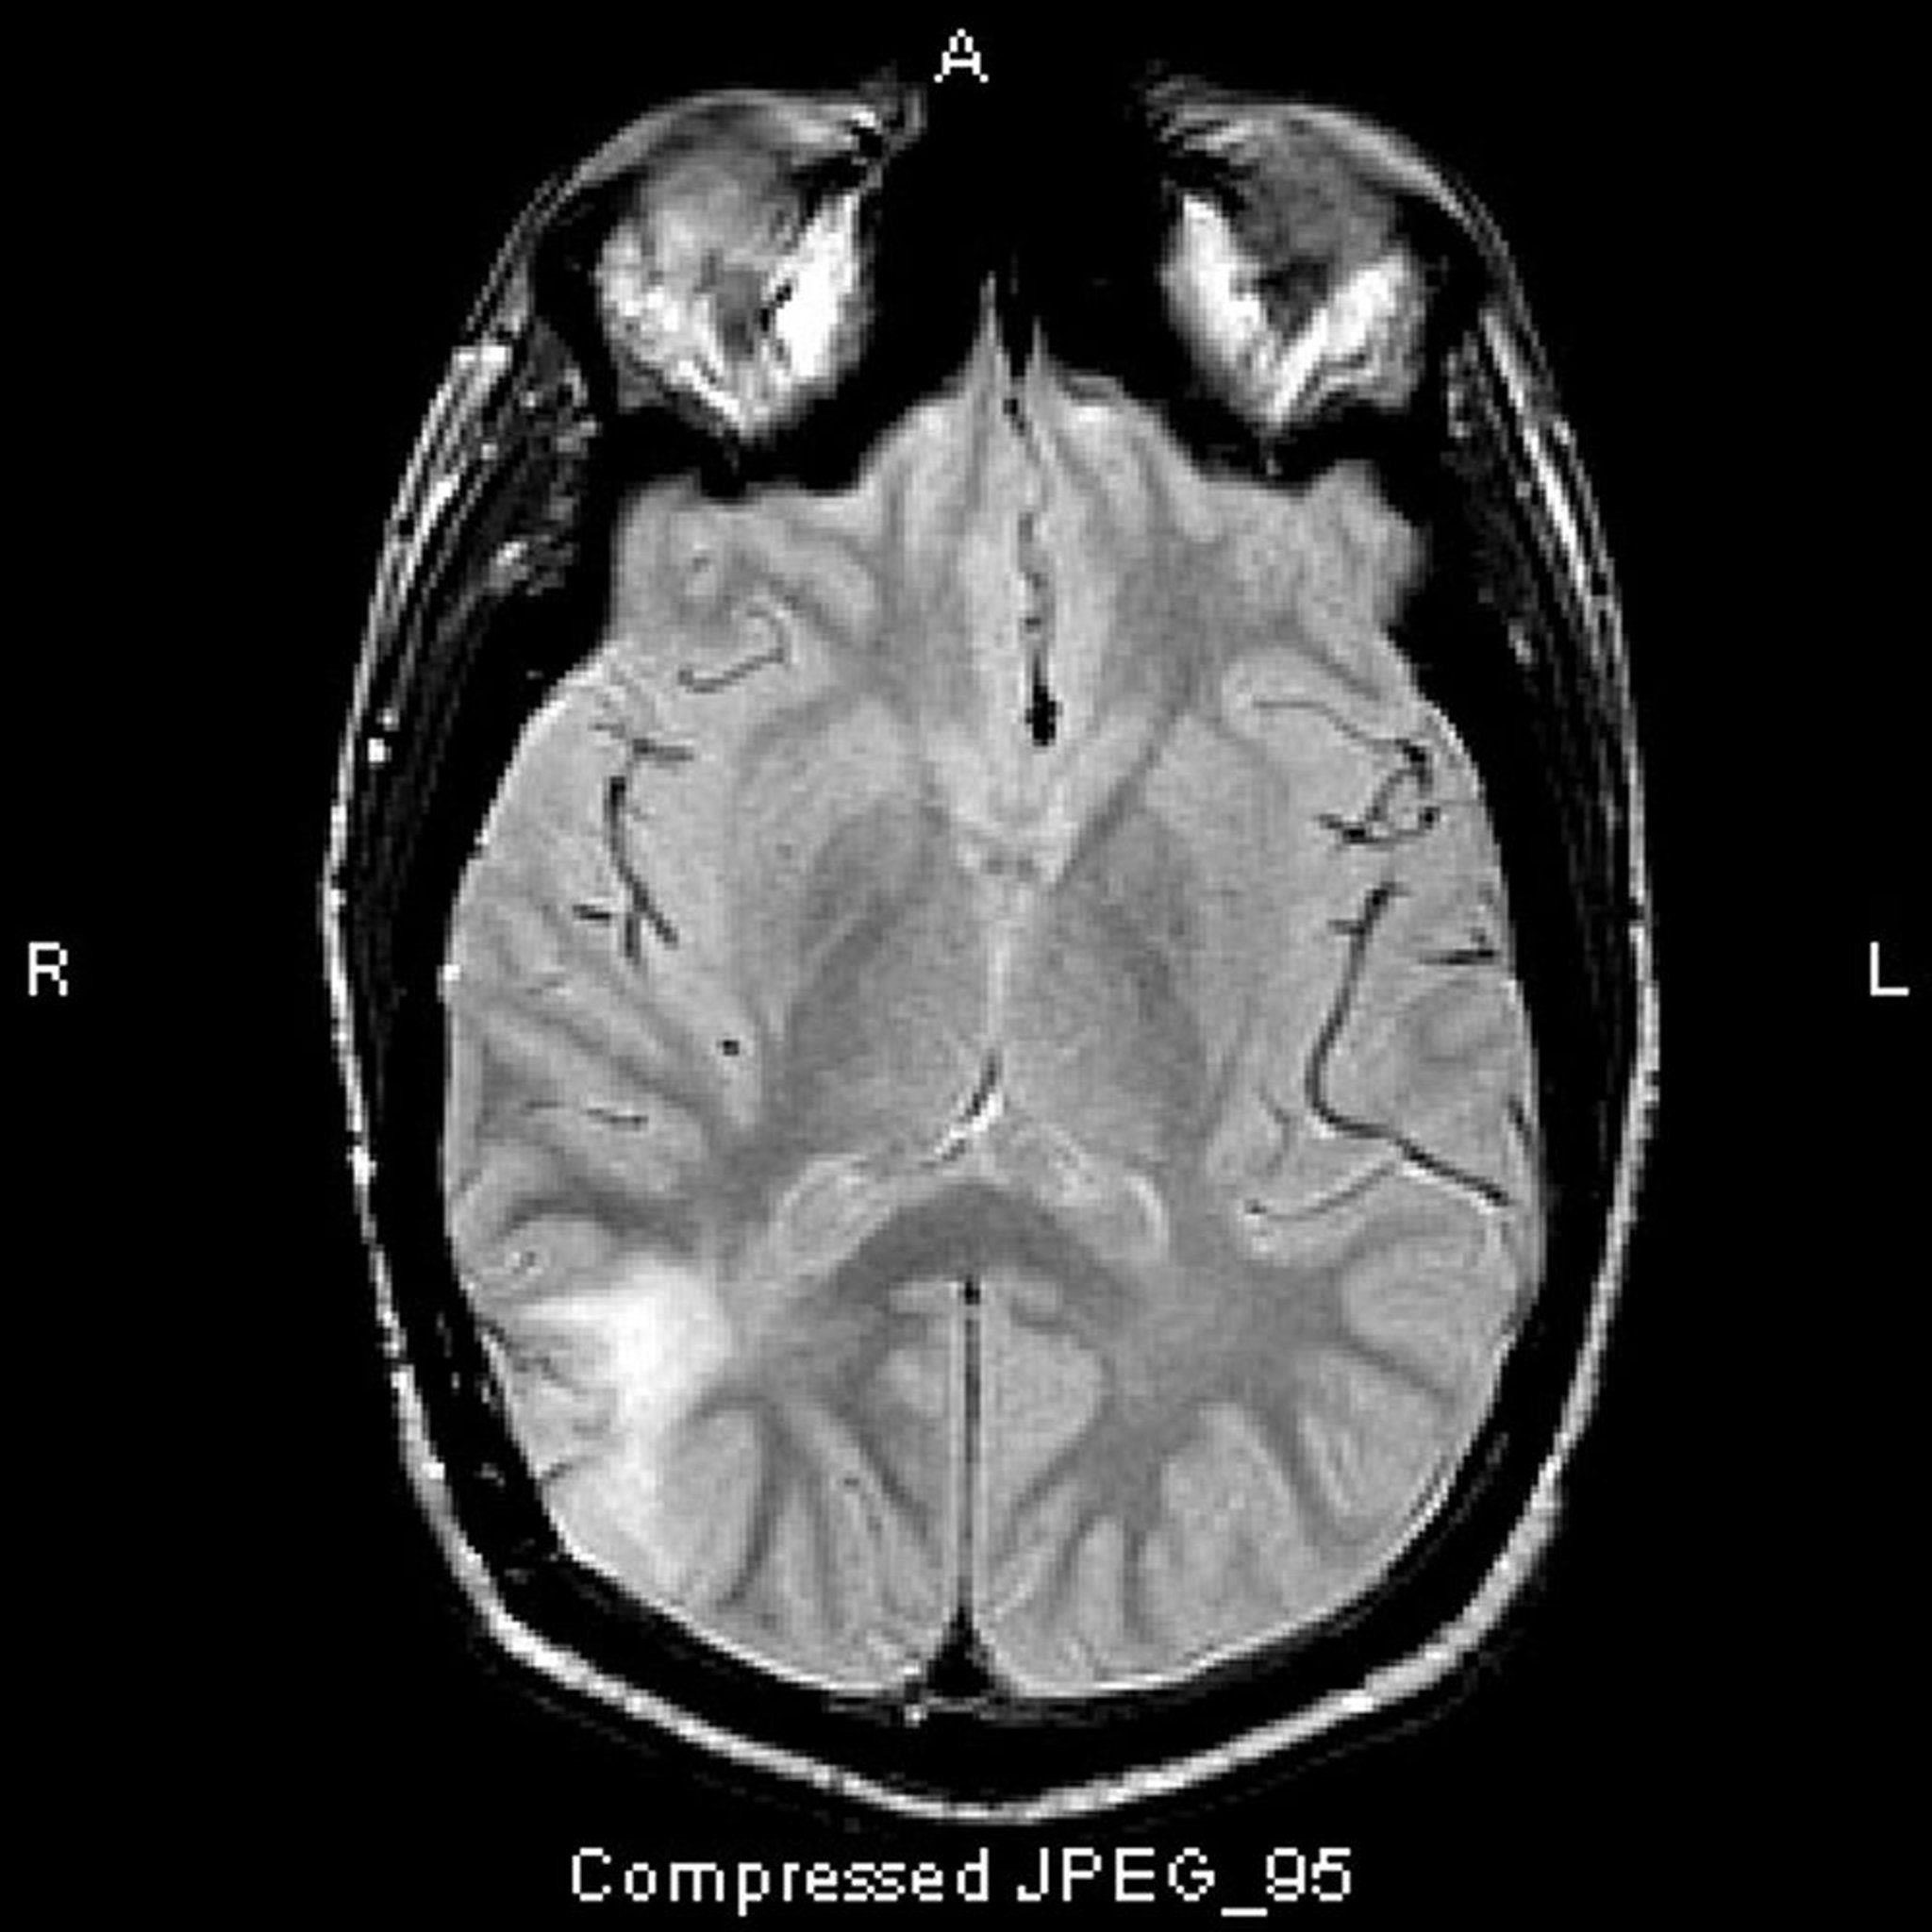

Astrocitoma anaplásico

Esta RM T2-FLAIR muestra una señal blanca en el lóbulo temporal posterior. La señal no es mejorada por el contraste. Es un astrocitoma anaplásico (grado III).

Image courtesy of William R. Shapiro, MD.